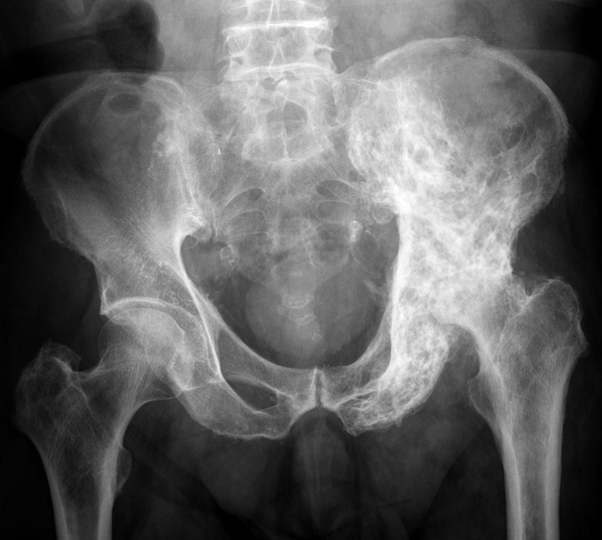

Pagets disease